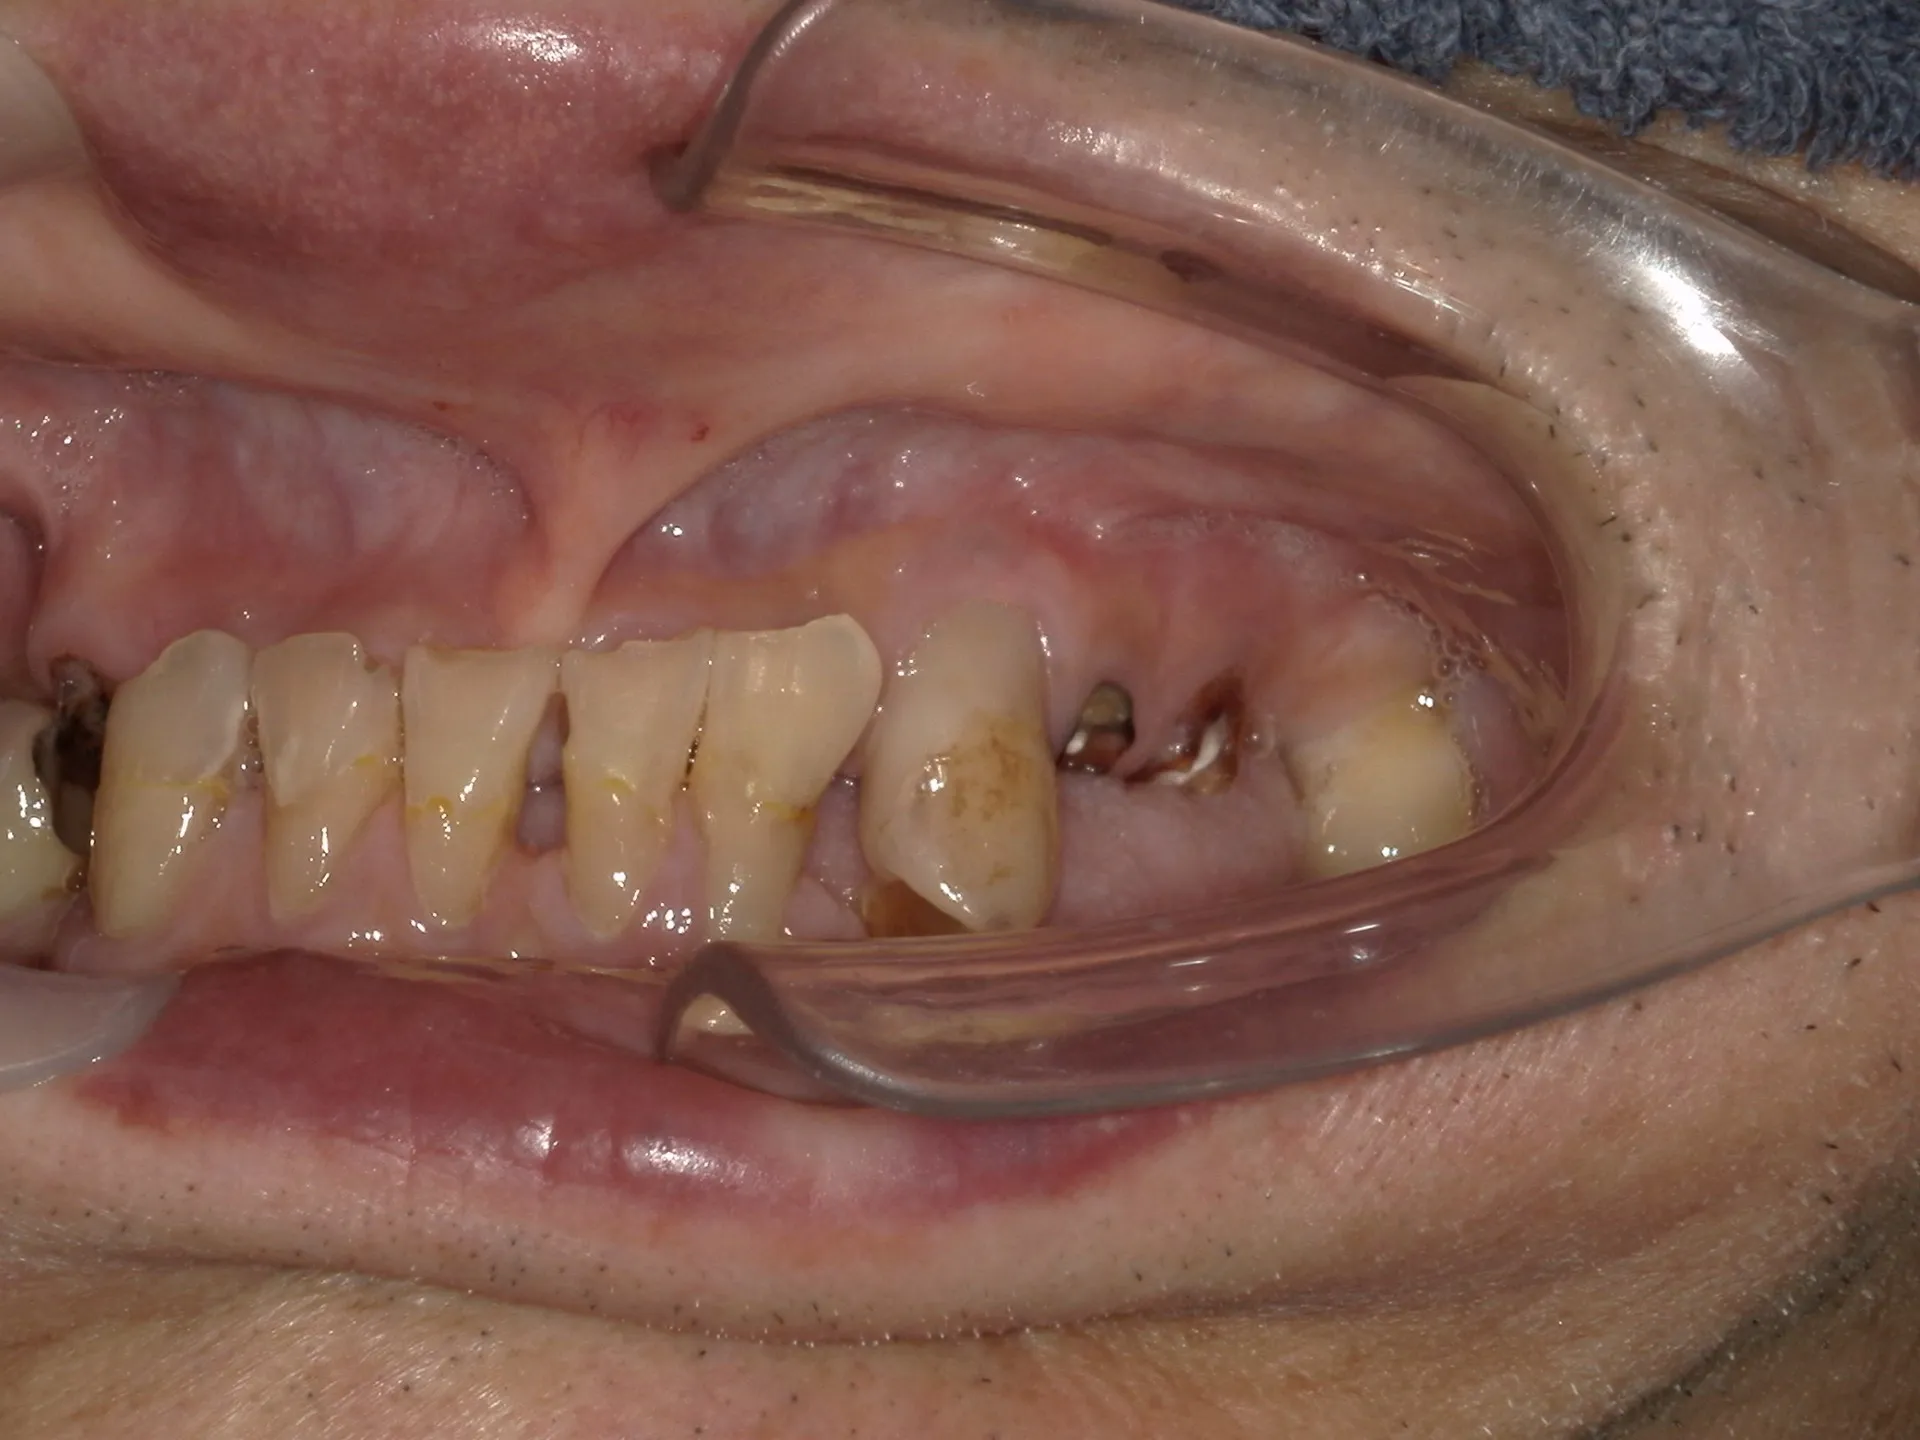

上記の写真は上下に歯があるものの噛むと歯が歯茎に当たるまで深く嚙み込んで入違った歯がすれ違って噛んでいることが分かります。

すれ違い咬合は上下の歯があるものの上下の歯が全く接触できないように歯が抜けてしまっているために無歯顎とほぼ同じように普通以上に噛み込んでしまい、歯が歯茎にぶつかるまで噛めてしまいます。